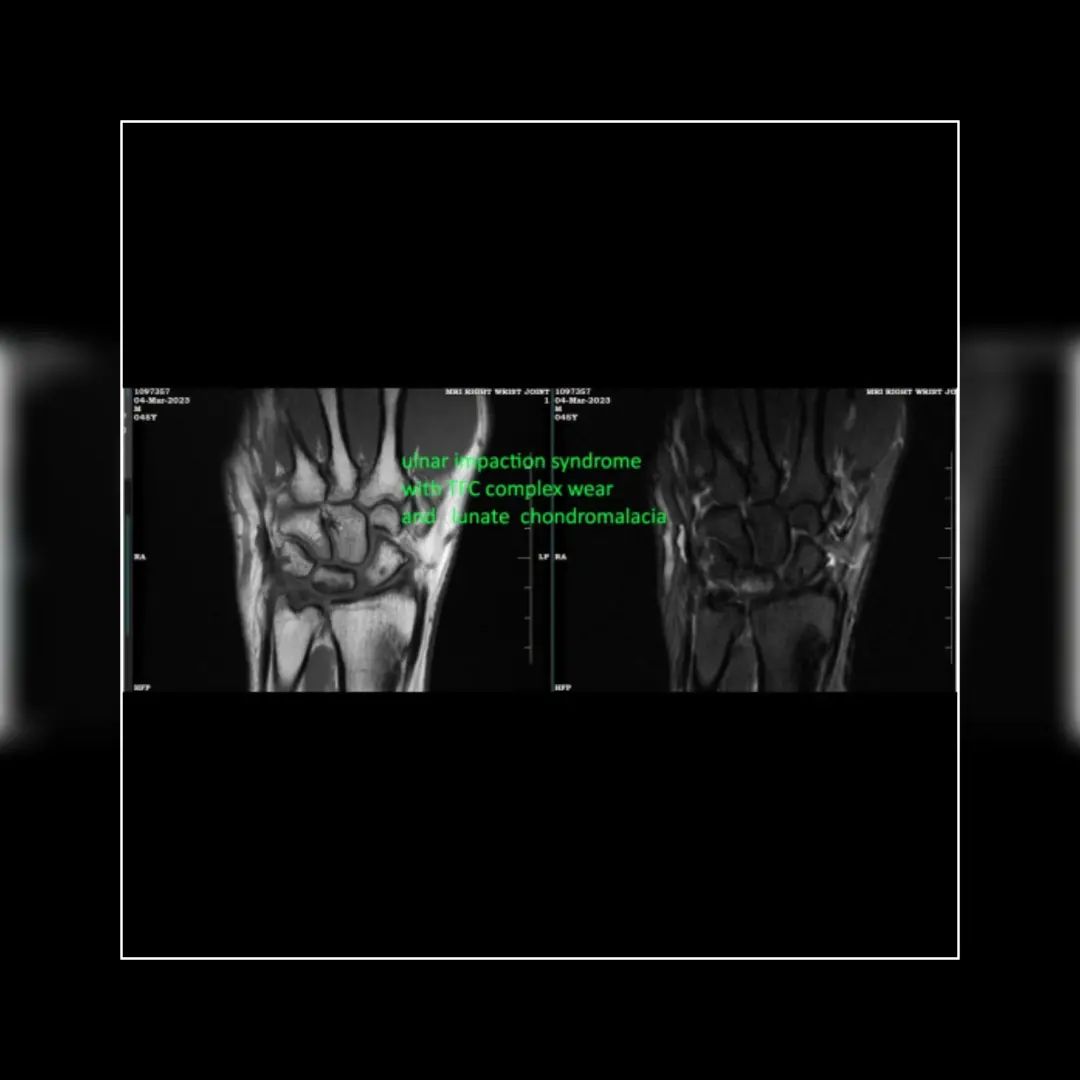

Multifocal small marrow edema involving the lunate, triqueteral bones

Thickened triangular fibrocartiliage complex ligament associated with trace ulnocarpal joint effusion with mild synovial thickening in this region.

*Features suggestive of ulnar impaction syndrome with TFC complex wear and early lunate chondromalacia*